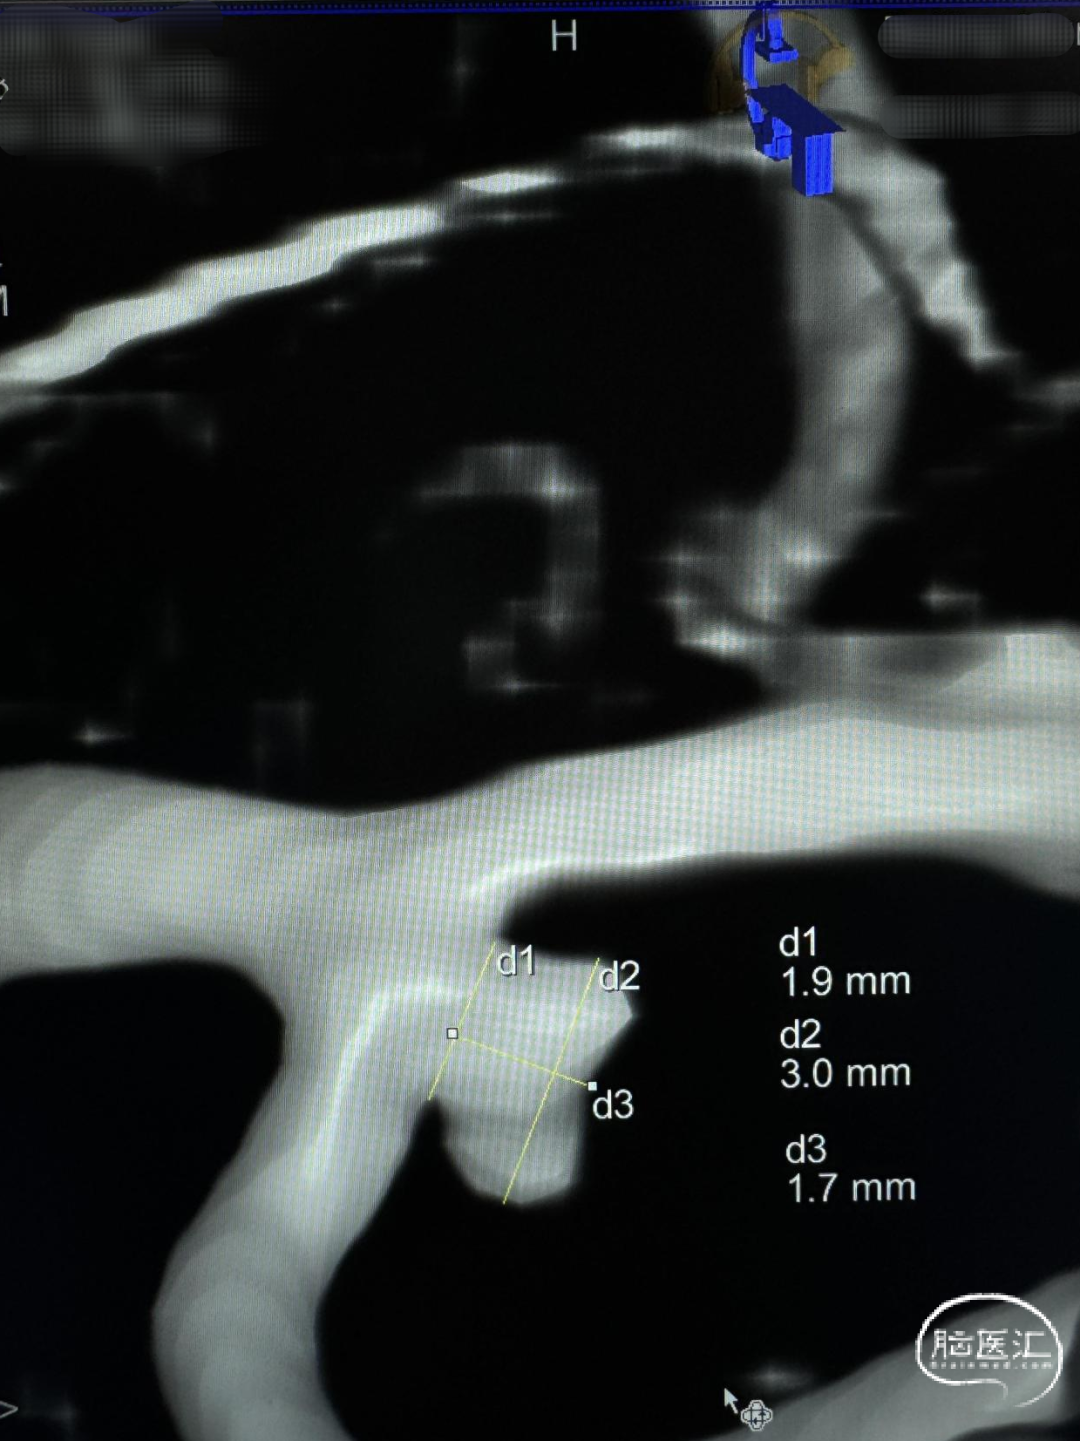

急诊头颅CTA:左侧大脑中动脉M1远端分叉处动脉瘤,左侧大脑中动脉M1段颞干分叉处动脉瘤。

左侧大脑中动脉M1段颞干分叉处动脉瘤

左侧大脑中动脉M1远端分叉处动脉瘤